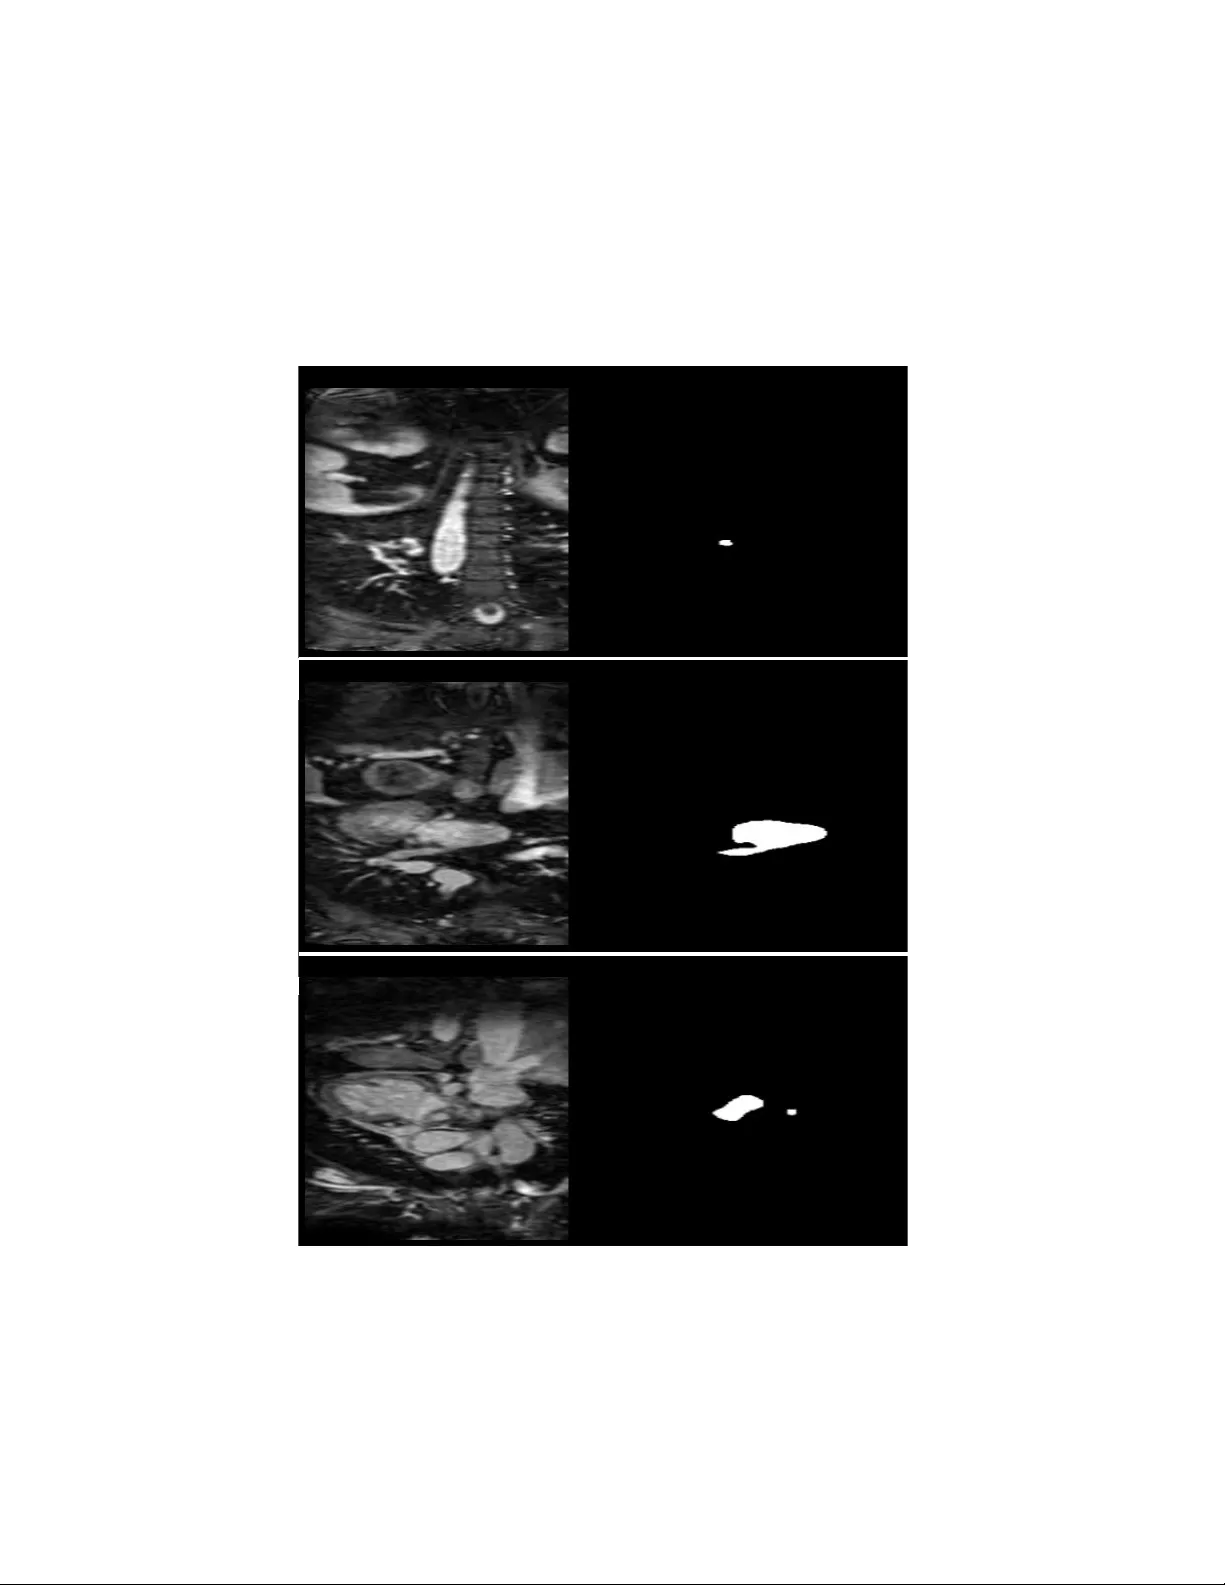

Left Atrial Segme ntation wi th nn U-Net Using MRI Fatemeh Hosseinabadi 1 , S e ye d ha ss a n S ha r if i 2 1 Assistant Professor of Radiology, Zahedan University of medical Sciences, Iran 2 Pediatric Cardiology Subspecialist, Day General Hospital, Iran Abs trac t Accurate seg mentation of the left atr ium (LA) from cardiac MRI is critical fo r guid ing atrial fib rillation (AF) ablation and constructing biophysical cardiac models. Manual delineation is time - consuming, observ er-dependen t, and impractical for large-scale or time-sensitive clinical workflows. Deep learning methods, particular ly convolutional architectures, have recently d emonstrated superior perfo rmance in medical image segmentation tasks. In this study, we applied the nnU-Net framework, an automated, self-configuring deep learning segmentation ar chitecture, to the Left Atrial Seg mentation Challenge 201 3 (LASC’13 ) d ataset. The dataset consists of thirty MRI scans with correspon ding expert- annotated masks. The nnU -Net model automatically adap ted its prep rocessing, networ k con figuration, and training pipeline to the characteristics of the MRI data. Mod el performance was quantitatively ev aluated using the Dice similarity coeff icient (DSC), and qualitativ e results were compared again st expert segmentation s. The propo sed n nU- Net model achieved a mean Dice score o f 93. 5%, dem onstrating h igh overlap with expert an notations and outperforming several traditional segmen tation approaches reported in previou s studies. The n etwork exhibited robust generaliza tion across variations in left atrial s hap e, contrast, and image quality, accu rately delineating b oth the atrial b ody and proximal pulmonary v eins. Keywords : Left atrium, MRI, nnU -Net, deep lear ning, segmentation, atr ial fibrillation . 1. Introd ucti on Atrial fibrillation (AF) is the most common sustained cardiac arrhythmia, affecting over 33 million people worldwide, and its prevalence continues to rise with aging populati ons. It is associated with a significantly increased risk of stroke, heart failure , and mortality, making accurate diagnosis and effective treatment critical. Catheter ablation has become a cornerstone therapy for AF, aiming to electrically isolate the pul monary veins and restore sinus rhythm. The le ft atri um (LA) plays a central role in the pathophysiology and treatment of AF, as its structure and morphology influence both arrhythmia initiation and ablation outcomes [1,2]. Precise knowledge of LA anatomy is therefore essential for preoperative planning, intraoperative navigation, and post -procedural evaluation. Three-dimensional (3D) anatomical models of the LA enable the visualization of patient-specific atrial geometry, f acilitate targeted ablation, and serve as input for biophys ical sim ulations that can predict electrophysiological behavior. However, constructing such models requires a ccurate segmentation of the LA from medical images — an inherently challenging and time -consuming task [3,4]. Magnetic Resonance Imaging (MRI ) and Compute d Tomography (CT) are the most commonly used imaging modalities for visualizing the LA . MRI offers exce llent soft tissue contrast and is preferred for assessing atrial wall fibrosis and scarring, whereas CT provi des superior spatial resolution and is widely use d for pre-ablation anatomical mapping. Neve rtheless, the segmentation of the LA from MRI or CT remains a challenging task due to factors such as low contrast between the atrial wall and surrounding ti ssues, variable blood pool intensit y, motion artifacts, and anatomical variability across patients. Traditional segmenta tion methods — such as region gro wing, thresholding, and 2 active contour mod els — often struggle to delineate thin atrial walls or to generalize across datasets with different acquisition protocols [5]. Ev en semi-automated techniques require substantial user interaction and exp ert correction, which limits t heir sc alability in clinical workflows. Therefore, robust automated segm entation methods are needed to enable reproducible, high -accuracy delineation of the LA and its associated structures. Recent advances in machine learning ( ML ) an d deep learning (DL) have improved medical treatment [6,7] and transformed medical im age analysis, particularly in classification and segmentation tasks [8,9]. Convolutional Neural Networks (CNNs) have de monstrated remarkable success in capturing complex spatial and contextual features, outper forming traditional techniques in both accuracy and robust ness. Among these architectures, the U-N et model int roduced a fully convolutional encoder – decoder structure with skip connections that preserve spatial detail while learning hierarchical representations. U-N et and its variants have become the de facto standard fo r biomedical image segme ntation across mul tiple modalities, including ca rdiac, bra in, and abdominal imaging. In c ardiac imaging, dee p learning – based segmentation has be en wide ly adopted for quantifying ventricular volumes, myocardial wall thi ckness, and atrial morphology. These automated systems provide faster and more reproducible results compared to manual deli neation, facilitating both clinical decision -making and computational cardiac modeling. Ho wever, developing deep learning models for medical segmentation typically requires careful network design, data preprocessing, and hyp erparameter tu ning, which can limit reproducibility and hinder adoption by non-technical users. To overcome these ch allenges, the nnU -Net (no-new-U-Net) framework was introduced as a self- configuring segmentation pipeline that automatically adapts to any ne w biomedical datas et without manual tuning [10]. nnU -Net dynamically adjusts preprocessing steps, network architecture, and training parameters based on the properties of the input data, providing a strong baseline that consistently ranks at the top of multiple segmentation benchmarks. Its built -in data normalization, patch-based training, and robust post-processing strategies make it pa rticularly well-suited for cardiac MRI segmentation, where anatomical variability and imaging noise are c ommon. In this study, we applied nnU- Net to the L eft Atrial Segmentation Challenge 2013 (L ASC’13) dataset, which provides high -quality MRI scans an d expert annotations of th e LA. Our objective was to evaluate nnU- Net’s ability to automatically segment the left at rium and compare its performance with traditional segmentation methods reported in previous literature. The model achieved a Dice similarity coefficient (DSC) of 93.5%, demonst rating excellent agreement with manual e xpert contours and confirming the potential of deep learning – driven segmentation for atrial fibrillation ablation planning and cardiac biophysical modeling. 2. Metho d 2.1 Data set De scr ipt ion Th is stu dy utili zed t he pub lic ly avai lable Lef t Atr ial Seg men tation C hal leng e 201 3 ( LASC’1 3) data set [ 11 - 13] , deve lope d join tly by King’ s Colle ge Lond on and Phi lip s Tech nologi e GmbH. The da tase t inc ludes 30 Mag neti c Res ona nce Imag ing (MRI) and 30 Com put ed Tomogr aphy (CT ) sca ns of pa tie nts with vario us card ia c con dit ion s. Eac h scan was ac qui red in 3D, pro vidin g high-r es olut ion vol umetr ic co verage of the left atriu m ( LA) a nd s urro und ing card iac struc ture s. I n t his st udy, we us ed 20 MRI scans for trai nin g, while the rema ining 10 scan s were reser ved for testing phase . The r efere nce an nota tions were pro duced by expe rience d ca rd iac ima gin g spec ialist s and inc lud e the left atri al ca vit y, a s hor t sect ion o f t he le ft a tri al a ppe nda ge ( LAA ), a nd t he p rox imal se gme nts of t he pul mon ary vei ns (PV s). In this stud y, we focuse d on the MRI sub set for deve lop ing and val ida tin g the segme nta tio n mod el. All data were anon ymi zed pri or to distr ibutio n, an d ethic al appr ova l for da ta shar ing was obt ained by the orig ina l ch alle nge orga nizer s. Figure 1Examples from the dataset with true labels 2.2 Data Pr epr oce ssi ng Pre proce ssi ng wa s aut omat ica lly hand led by the nnU-Ne t frame wor k, wh ich op timi ze s its data pipe line acc ordin g to data set cha racte ris tics. The ima ge s were firs t resa mple d to isot rop ic voxe l spac ing to en sure c onsist en t spati al res olu tion acro ss pa tien ts. Inten sity value s wer e norma lized to zero mean an d 4 uni t vari anc e, im provi ng th e st abilit y of ne twor k train ing . Eac h MRI v olu me wa s cropp ed arou nd the car diac r egio n to rem ove irre levan t bac kgro und and red uce c omputa tiona l ove rhe ad. T he da tase t was spl it into train ing ( 70%), valid ation (1 0%), and te sting (20%) subs et s u sing pati en t-le vel separa tion to pr eve nt data leakag e. To enhan ce robus tnes s and reduc e ove rfit tin g, data augmen tation was appl ied on -th e-fly, inc lud ing: Ran dom r otat ions a nd flips , E la sti c defor mat ions , G amma co rrec tion and br igh tne ss shift s, Addit ive Gaus sia n noi se. T his c ombi na tio n e nsure d the mod el coul d gen era lize we ll to varia tions in atr ia l or ient ati on, inten sity, an d im age q uali ty. 2.3 Mode l Ar chite ct ure We em plo yed the 3D full- resol uti on nnU-N et arch ite cture , which bui lds upon the sta ndard U-Net str uctur e w ith se vera l key inn ova tions: • An enc ode r – deco der des ign wit h skip connec tions to reta in sp atia l con text while enab lin g de ep fea ture ext rac tion. • Re sid ual co nvol uti ona l blo cks with insta nce norm al iza tio n an d leaky ReLU acti vati on for sta ble tra inin g. • A deep sup ervis ion mec han ism, where auxil iary outp uts fro m inte rmed iate deco der le vels co ntr ibute to the overa ll los s fu ncti on. • Dy nam ic patc h size sel ect ion and ba tch size optimiz ation au tomati cally dete rmi ned by the fr ame wor k ba sed o n a vai labl e G PU mem ory and i nput im age di mensio ns. Un lik e manua lly tune d mod els , nnU-Ne t sel f-c onf igur es all hype rpara met ers (e .g., kerne l si ze, nu mber of featu re map s, net wor k dept h) acco rding to the prope rties of the inp ut dat ase t, ens uri ng op tima l ad ap tati on to LA s egmen tat ion . 2.4 Tra inin g Pr ocedu re Tr ain ing was cond ucte d usin g the PyT orc h i mple menta tio n of nnU-Ne t (v2. 1). The mode l was tra ine d on an NVIDIA RTX A60 00 GPU with 48 GB VRAM . The fol low ing key para meter s were au tom atic ally co nfig ure d by nn U-Ne t: • Lo ss func tion : Co mbine d Di ce loss an d c ros s -en tr opy los s, encour aging bo th re gio nal o ver lap an d v oxel-w ise cla ssif ica tion ac cur acy . • Op timi zer: Stoc hasti c Gradi en t De sce nt (SGD) with mome ntum = 0.99 and we igh t decay = 3× 10⁻ ⁵. • In iti al lear ning r ate: 1×10⁻² wi th a pol yno mial de cay sc hed uler . • Ba tch siz e: 2 (du e to 3D pa tc h tr ai ning ). • Ep och s: 100 0 itera tions (appro xima tely 50 0 epoc hs, de pendi ng on patch sam pli ng) . Du rin g tra inin g, dee p supe rv ision was used to improve gra dien t pro paga tion thr ough the netwo rk, wh ile slidi ng-w indow infe rence wa s app lied duri ng test ing to hand le fu ll-si ze 3 D vol ume s. T he model re qu ired appro ximate ly 36 hou rs of train ing to c onver ge on the MRI data set . 2.5 Eval uat ion Me tr ics Th e seg ment at ion perfo rman ce was asse ssed usi ng se vera l quan tit ati ve metri cs wide ly adopt ed in car diac imagi ng benchm arks includ ing Dice whic h meas ures the over lap betw een the tr ue mask and pr ed icted mask by the mode l, Hau sdor ff Dista nce (H D, 95 th perc ent ile ) whi ch mea sure s bounda ry de via tion be twee n automa ted an d manua l con tours, a nd Ave rage S urfa ce D istanc e (AS D) th at qua ntif ies the mea n bou nda ry d istanc e acr oss a ll co rre spond ing sur face points . Ou r mod el ach ieve d a mean Dice coef ficie nt of 93.5% , ind icati ng excel lent sp atia l agree me nt with ex per t segme ntat ions . The 95th perce nti le Hau sdor ff dista nce wa s 3.2 mm, an d the aver age surfac e dis ta nce wa s 1. 1 mm, dem ons tra ting hig h ge ometri c accu racy a nd smo oth bound ary de linea tion. 2.6 Imple menta tion D etails All expe rimen ts were condu ct ed usin g Pyt hon 3.10 , Py Tor ch 2.2, and the nnU-N et fra mew or k (I sensee et al. , 20 21). The mode l trai nin g and eva luat ion were pe rfor med on Ubun tu 22.0 4 LT S wit h an Int el Xe on 6248 CPU and 256 GB RAM . Vi sua lizat ion and resu lt insp ectio n were carr ied out usi ng IT K- SNA P and 3D Slice r. The tra ine d mode l and conf igura tion file s were store d for re prod ucibi lity , and al l prep roce ssi ng , au gment ation , and infe ren ce pipe line s fo llow ed the standa rd nnU-Ne t conv ention s to ensur e c ompa rabil ity wit h e xisti ng litera ture . 3. Resul ts 3.1 Quan tit ative Perf ormanc e Th e pro pose d nnU-Ne t model demo nstr ate d out stan ding perfo rmance in the aut omat ic segme nta tio n of the left atr ium (LA) from MRI vol umes in the LA SC’ 13 dat ase t. Acro ss the te st set, the mode l ac hieved an avera ge Di ce Simi lar ity Coe ffi cie nt (DSC ) of 93 .5% ± 1.8, indic ati ng hig h s patia l over lap be twe en auto mat ed and expe rt manu al segm ent atio ns. In addi tio n, the 95th perc entil e Haus dorff Dis tance (H D95) was mea sure d at 3.2 ± 0. 9 mm , wh ile the Ave rag e Sur face D istanc e ( ASD) was 1.1 ± 0. 4 mm, re fle cti ng excel le nt bo undary con for mity an d smo oth sur face re pres en tati on. Thes e resu lts de mon stra te tha t the mode l is capa ble of cons istentl y deli nea tin g the atr ial ca vity, pulm ona ry vein inl et s, a nd sh ort tru nk of the left atri al a ppenda ge (L AA) wi th near-e xper t prec ision. 6 Figure 2Left: original image, center: true mask, left: predicted mask by the model Tabl e 1 . Qua ntit ati ve segm ent atio n pe rform anc e of the nnU- Net model on the LASC’1 3 MR I tes t data set. Me tric Me an ± SD Bes t C ase Wor st Case Dic e Simi lari ty C oef fic ient (DSC ) 0.93 5 ± 0.018 0.95 8 0.90 1 Hau sdor ff Dist ance ( 95%) [mm] 3.2 ± 0. 9 2.1 4.8 Ave rage Su rfac e Di sta nce [mm] 1.1 ± 0. 4 0.7 1.8 3.4 Mode l R obustn ess and Ge nera lizat ion Th e nnU- Net mode l showe d exce llen t robu stne ss ac ross var yin g imag e con tra sts and ana tomic al va ria tio ns. The mode l’s se lf -c onfig urin g design , inc lud ing a utoma tic n or mali zat ion , data au gmen tatio n, and patch-b ased trai nin g, contr ibu ted to its gener al iza tio n capab ili ty. Nota bly, cases wit h stro ng mot ion art ifacts or par tia l at rial visib ili ty stil l prod uce d Dice sco res abov e 0.90 , de mon stra ting res ilienc e aga inst impe rfec t imagi ng con dit ion s. Visua l inspec tio n also co nf irmed that nnU -Ne t pres erv ed fine anato mical de tai ls, suc h a s pulm ona ry vei n orif ices an d LAA ba se s truct ure s , wh ich are c lin ica lly re levant for abla tion p lann ing. Com par ed to manua l deli nea tion , nnU- Net ac hieved com par able acc ura cy while red uci ng segme nta tion ti me from sever al minut es per ca se to le ss tha n 10 sec ond s per 3D vo lume dur ing i nfer ence. 3.5 Stat ist ica l V ali dati on To e nsure robu stne ss of the resu lts , a fiv efo ld cro ss-v alida tio n w as p erf ormed on the M RI su bse t. T he Dic e score s acr oss fol ds were con sisten t (ran ging fr om 92. 8% to 94. 1%), con fi rmi ng stab le mode l pe rfo rma nce . A paire d Wil coxon signe d-rank test com par ing auto mate d an d man ual segme ntati ons sho wed no stati sti cal ly signi fic ant diffe rence (p > 0.0 5) in volu metric mea sure ments , rei nfor ci ng the mod el’s rel iab ility for clini ca l us e. 4. Discuss ion 4.1 Pri ncip al Fin ding s In thi s study , w e appl ied the nnU- Ne t deep lea rnin g frame wor k f or auto ma ted seg ment at ion of the lef t at riu m ( LA) f rom card iac M RI usin g the Left At ria l S eg ment at ion Chal lenge (LA SC’13) data se t. The mod el achie ved a mean Dic e Sim ilar ity Coeff icien t (D SC) of 93. 5%, a Hau sdo rff Dista nce (95%) of 3.2 mm, and an Aver age Surf ace Di stan ce of 1.1 mm, out per for min g severa l tra ditio na l an d deep- le arn ing -ba sed meth ods pre viou sly rep orte d on this data set . Th ese resu lts high light nnU- Ne t’s ca pabili ty to deli ver r obust , hig h -pr eci sio n seg men tat ion of the LA and its su bstru ctur es witho ut ma nua l hyper parame ter tunin g or data set-sp eci fic opti miz atio n. The model’ s pe rfo rma nce indi cat es its ab ili ty to captu re fine stru ctura l deta ils such as the left atria l appe ndage (LAA ) an d pulmo nary ve in (PV ) inlet s, whic h are esse nti al f or pat ient -s pec ific mod eli ng an d abla tio n guida nce. Th is is par ticu larly imp or tan t in the con text of at ria l fibri lla tion (AF), wher e accu rate rep resen tat ion of atria l geom etr y dir ectly inf luence s cathe ter navi gat ion , lesio n targe ting, and sim ula tion accu rac y in car diac el ect roph ysiol ogy. 4.2 Comp ari son wi th Previo us App roa ches His toric all y, left atria l segme nta tion has rel ied on semi -au tom ate d or atla s-ba sed method s, such as re gio n grow ing , stat ist ica l sh ape model s (S SMs ), or defor mable regi stra tion frame works. For exa mpl e, To bon -Go mez et al . (2 015) a nd other LASC’ 13 par tic ipants report ed Dice coe fficie nts rang ing be twe en 84% and 90%, dep end ing on the moda lity and alg orith mic de sign . Whi le thes e tec hniq ue s pr ovi ded anat omi cal ly consi ste nt seg men tati ons , the y were lim ite d by depe nde nce on ini tializ atio n, int er- patie nt a nato mica l varia bilit y, a nd d iff icul ty gen era lizing acro ss data se ts. By co ntra st, nnU- N et’ s self -co nfig uri ng pipe line overc omes the se issu es by aut omatic all y tai lori ng pr epr oce ssi ng, arc hitec ture dept h, and patc h siz e to the dat a dis trib uti on. The inclu sion of dee p sup ervis ion and res idua l con nec tio ns enh ance s gradie nt flow and feat ure consi ste ncy acr oss scale s, al low ing the netw ork to lea rn both globa l anato mic al conte xt and loca l bou ndary deta ils. Con se que ntl y, nnU- Net ach ieve d up to 9% impro vemen t in Dice acc uracy comp ared wi th tra ditio nal me tho ds and riv ale d the pe rfo rmanc e of more rec ent cu sto m deep-l ear ning mode ls trai ned on larg er da tase ts. 4.3 Clin ic al I mpli cat ions Ac cura te and repr oduci ble LA segm enta tion has criti ca l impl icati ons for AF ab lati on plann ing an d bio physi cal card iac model ing . Detai led 3D rec onstr uc tio ns of the LA all ow clin ician s to visu alize co mpl ex ana tomica l fea ture s — such as the num ber, orie ntat ion , and dia meter of pul mon ary vein s — an d to pla n a blat ion strate gies ta ilor ed to each patie nt. Add iti ona lly , segme ntat ion outp uts can be dir ectly used in compu tation al elec tro physio logica l s imu lat ion s to mod el wave pro pa gati on an d asse ss ar rhy thm ia r ecu rren ce risk . T he a bil ity of nnU-N et to p er for m ful ly a utoma ted s eg men tati on i n un der 10 se con ds per case offe rs a sign ifica nt advant age f or cli nica l tran slati on. I ntegr atin g such mode ls into ima ge-gu ide d elec troph ysio log y syste ms co uld substa ntia lly redu ce pre- proce dura l prepar atio n time , sup port intra- proce dura l upd ates, and enhan ce repro duci bilit y acr oss imag ing cente rs. Fur ther more , 8 the elim ina tio n of man ual d eli neati on re duces in ter-o bse rver var iabi lit y, p romoti ng st anda rd iza tio n in AF imagi ng work flows . 4.4 Robu st ness an d I nter pre tab ili ty On e of the key stren gths of nnU- Net lies in its self-a dap tive conf igura tio n. Unlik e co nve nti onal CNNs re qu irin g manual tunin g, nnU-N et auto matica lly conf igure s its networ k topo log y an d train ing pa ram ete rs base d on datas et prope rties , en sur ing opti ma l perf ormanc e acr oss divers e imag ing mod aliti es . The mode l’s consi ste nt D ice sc ore s ac ross cro ss-v alida tio n f old s co nfi rm its robus tnes s to int en sit y i n ho mogene ity , mo tio n ar tif acts, and ana tomic al varia bilit y in here nt in car diac MRI. Alt hough deep learn ing mode ls are ofte n cri tici zed for the ir “b lack - box” nature , nnU - N et’ s feat ure vis ua liza tion and predi ct ion map s de mons tra te spa tial cohere nce wit h expec ted anat omi cal bounda ries. Th e netwo rk’ s ab ili ty to re produ ce exper t -li ke con tou rs wit hout ex plicit sup ervis ion on st ruc tura l la ndm ark s refl ect s its ca pac ity for dat a-d rive n ana tomi ca l lear ning, an import an t step t owar d cli nic all y tr ust wor thy AI in car diac i mag ing. 4.5 Limit atio ns a nd Futu re Wor k De spi te the stro ng resu lts, seve ral lim ita tions must be ackn owled ged . Fir st, this stud y wa s limi ted to the MRI subs et of the LASC’ 13 da tas et; theref ore, perfor mance gener al izati on to CT or other MRI pr oto col s r ema ins to be valid ate d. Diffe ren ces i n vo xel re solu tio n, contra st, a nd scan ner manuf acture r ma y inf luence the mode l’s tra nsfer abil ity . Secon d, wh ile nnU -N et prov ides auto ma tic conf igura tion , it req uire s su bst anti al c ompu ta tio nal reso urce s f or 3 D tra inin g a nd infe re nce. A lthou gh infere nce time is rap id, tra inin g on high- res olu tio n car diac MRI vol umes may be imprac tic al on lower-e nd GPU s. Th ird , the data set’s modera te size (30 MRI case s) res trict s the expl ora tio n of gene ral iza tio n acros s pa tho log ical subgro ups or rare ana tom ica l varian ts. Fu tur e re search sho uld incorp orate mult i-ce nter da tase ts w ith l arge r sa mple siz es and div ers e acq uisi tio n prot oco ls to e val uate t he ge nerali zabil ity a nd ro bus tne ss of the frame work. Addit iona lly, man ual an nota tions, even by e xper ts, ar e sub jec t to inte r- obs erver va ria bil ity , wh ich c an i nf luenc e gr ound -tru th acc uracy . Fu tur e studie s wil l foc us on ex tend ing this wor k in severa l dire ct ions . Fi rst , the integ ratio n of multi - mod ality data (MRI and CT) cou ld enha nce mode l robu stne ss acr oss imagin g pro toc ols and ena ble cr oss- domai n ge nera liz atio n. Sec ond, incorp ora ting atte ntion mec han isms or tran sfor mer-ba sed arc hitec ture s may fu rthe r impr ove the ne twork ’s abi lity to c ap ture l ong - ran ge depe ndenc ies wit hin the LA stru cture . Third , com bin ing se gme ntatio n with func tio nal imag ing (e .g., late gadol iniu m en han cem ent MRI ) cou ld pro vide both struc tura l and tis sue-c har act eri zat ion insi ghts , ena bli ng co mpre hensi ve mode ling of atr ial rem odel ing in A F. In add iti on, se mi-su pe rvis ed le arnin g and fe dera ted lear nin g f ram ewo rk s c oul d facil itate la rge-sc ale mode l tra inin g w hil e prese rving p atie nt pr ivac y and add res sin g data scarc ity. Prospe ctive vali dat ion in clin ica l en vir onmen ts will also be es sen tial to eva luate the model ’s impa ct on wo rkf low effi cie ncy , ablat ion su cc ess r ates, and pr ocedu ral out comes . 5. Conclu sion Th is stud y dem ons trates the effec tivene ss of the nnU -Net dee p lear nin g frame work for full y auto mate d se gme ntatio n of t he le ft a triu m ( LA) fr om MRI data. Usin g the LA SC’ 13 datase t , t he pr opose d model ac hieved a mean Dic e coef ficien t of 93 .5%, outpe rfo rmi ng tradi tio nal region -gr owing and sta tis tica l mod el-ba sed appr oache s whi le requ iring no manual co nfig urati on or par ame te r tuning . The resu lts co nf irm tha t nnU- Ne t can acc ura tely and eff icien tly de linea te key anat omi cal struc tures — incl udi ng the lef t atr ial body, appen dage, and pulmo nary ve in inle ts — pro vidi ng seg ment ation qua lity co mpar able to e xpe rt manua l anno tatio ns. Su ch prec isi on is v ital fo r atria l fibr illa tion a blat ion pla nnin g , car dia c biop hysica l simu la tion s, and qua ntita tiv e atri al rem ode lin g studi es. Beyo nd its stron g pe rfo rma nce , nnU- N et’s se lf-c onfig urin g de sign and high inf ere nce speed (< 10 sec onds per c ase) ma ke it high ly suita ble for integra tion into clin ical wor kflo ws , enab lin g repr oduci ble and opera tor- ind epend ent LA mode lin g. Fu ture work will f ocus on exte nding th is frame work to mul timoda l im ag ing (M RI a nd CT) , incorp ora ting tis sue cha rac teriza tion, and ex plorin g trans for mer -ba sed and multi moda l arc hitec ture s to fur ther impr ove anato mic al f idel ity a nd c linic al appli cab ili ty. Eth ic an d D ata Stateme nt: Th e data set use d in this stu dy or igi nate s from th e Left Atr ial Segme nta tion Cha lle nge (LA SC’13) , ini tia lly intr oduce d by Tobon-G omez et al. [ 11 ] in the ir benc hmar king wor k publi shed in IEE E Tr ans act ion s on Med ical Im agin g and furth er suppo rted by subse quen t me tho dol ogic al paper s in Me dica l Ima ge Ana lysis a nd Fr ontie rs in Ph ysio logy . Both jour nals hav e c onf irme d and de cla re d t hat al l im agi ng d ata were coll ec ted in acco rdanc e with insti tut iona l eth ica l sta nda rd s and re leva nt re gu lati ons . Ref erences [1] Lipp i G, Sanch is-Go mar F, Cerve llin G. Global epidemi ology of atri al fib ril lati on: an incre as ing epid emi c and public hea lth cha llen ge. Int erna tio nal jour nal of str oke. 202 1 F eb;1 6(2) :217- 21. [2] Pongr atz J, Riess L, Hartl S, Brue ck B, Tesc he C, Ol brich D, Wanke rl M, Dorwart h U, Hoffma nn E, Stra ube F. Com para ti ve a nalysi s of left atri al si ze a nd appe ndag e mo rphol ogy in paro xys mal and persist ent at rial fi bril lati on p ati ents . Jou rnal of Ar rhyt hmia . 20 25 Fe b;41 (1): e132 24. [3] Bons o A, F ant inel M, Scalchi G, F err ara S, India ni S, C alore F, Licc iarde llo C. Left atri al mode l recon str ucti on in atr ia l fib ril lati on abla tio n: rel iab ili ty of ne w map ping and co mple x impeda nce sys tems . Ep Euro pace. 2017 N ov 1;1 9(11) :18 04- 9. [4] Lin H, L ópez- Tapi a S, Sch iffer s F, W u Y , G unaseka ran S, H wang J , Bis hara D, K holm ovski E , Elbaz M, P assma n R S, Kim D. Usf orme r: A sm all netw ork f or l eft a tri um se gmenta tion o f 3D LG E MR I. Hel iyon . 2024 Apr 15; 10(7 ). [5] Daou di A, Mahmou di S, Chikh MA. Auto mati c se gmen tatio n of the le ft atri um on CT image s. InI nte rnat ion al Worksh op on St ati stical Atlas es a nd Comp uta tio nal M odel s of th e Hea rt 2013 Sep 26 ( pp. 1 4-23 ). Berli n, H eide lberg: S pringe r B erlin Hei delber g. 10 [6] Norouz i F, Ma chad o B L. Predict ing Menta l H ealt h Out comes: A Machine L ear ning Approac h to Depres sion, A nxiety, and St ress . I nter nati onal Journa l of Ap pli ed D ata Scie nce in Engi neer ing and Hea lth. 2024 Oct 31; 1(2):98- 104. [7] A si f S, Wenhui Y, ur-Rehm an S, ul-a in Q , Amja d K, Y ueyan g Y, J inhai S, Awai s M. Advanc eme nts and pros pects o f mac hine l earnin g in m edica l diagnos tics : unv eili ng th e f utur e of di agnost ic pre cision . Arch ives o f C omput ational Metho ds in Engi nee ring . 20 25 Ma r;32(2) :853 -83. [8] A bbas i H, Afra zeh F, Ghase mi Y, Gha semi F. A sh all ow revi ew o f arti fic ial i ntellig ence a ppli cations in brain disea se: st roke , Alzh eimer' s, and aneu rysm. Inter nat iona l Journa l of Appl ied Data Sci ence in Engine ering and Healt h. 2024 Oct 5;1( 2): 32- 43. [9] Jiang J, Ra ngne kar A, Veerara ghav an H. Sel f‐super vis ed lear ning improve s robu st ness of deep learn ing lung tumor se gment ation m odel s to C T imagi ng d iffe rences . Medic al P hysics . 2 025 M ar; 52(3) :15 73- 88. [10] Isens ee F, Jaege r PF, Kohl SA, Pet erse n J, Maie r-Hei n KH. nnU-Net : a sel f-co nfig uring met hod for deep learni ng- bas ed biom edic al ima ge se gmentat ion. Na tur e met hods . 2021 Feb ;18( 2):2 03- 11. [11] Tobon -Gom ez C, Geers AJ, Peters J, Wees e J, Pinto K, Kari m R, Ammar M, Daoudi A, Marg eta J, San doval Z, St ende r B. Benc hmar k for algor ith ms segmen ti ng the left atrium from 3D CT and MRI datas ets . IEEE tra nsac tio ns on medi cal i magi ng. 2 015 Feb 3;3 4(7): 1460 - 73. [12] htt ps:/ /www .kag gle.c om/data set s/ad ars hsng/ heart- mri -imag e-da tas et-lef t-at ria l-se gmen tati on/dat a [13] Tobon-G omez C, Pete rs J, Weese J, Pint o K, Kar im R, Sc haef fte r T, Raz avi R, Rho de KS. Lef t atri al se gmen tati on cha lle nge: a unifi ed benchm arki ng framew ork. InInte rnat ional W orks hop on Statis tical A tlas es and Comput ationa l Models of t he Hea rt 2013 Se p 26 (pp. 1-1 3). Ber li n, H eid elber g: Spr inger Be rli n Hei delber g.